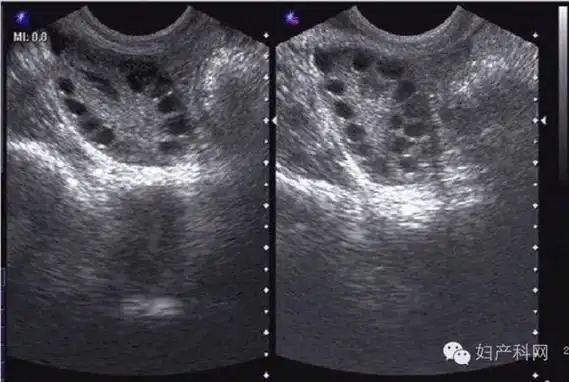

3,多囊卵巢,单侧或双侧有大于或等于12个小卵泡.